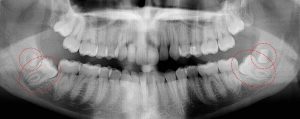

This 19 year old patient has all four 3rd molars present (circled). The roots are +90% formed. Both lower 3rd molars are impacted against the 2nd molars with no chance of further eruption and a +60% probability of decaying before age 30. The patient presented with pain and infection around both lower 3rd molars, requiring immediate extraction